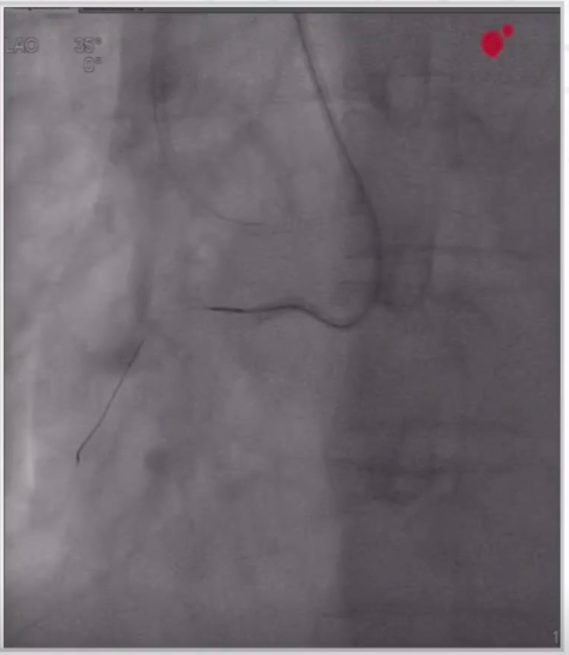

9月前初次冠脉造影结果

1、术前造影显示LAD弥漫病变、中段完全闭塞,LCX原支架血流通畅,RCA血管纤细、中段完全闭塞,远段侧枝循环形成。

LAD造影图像

RCA造影图像